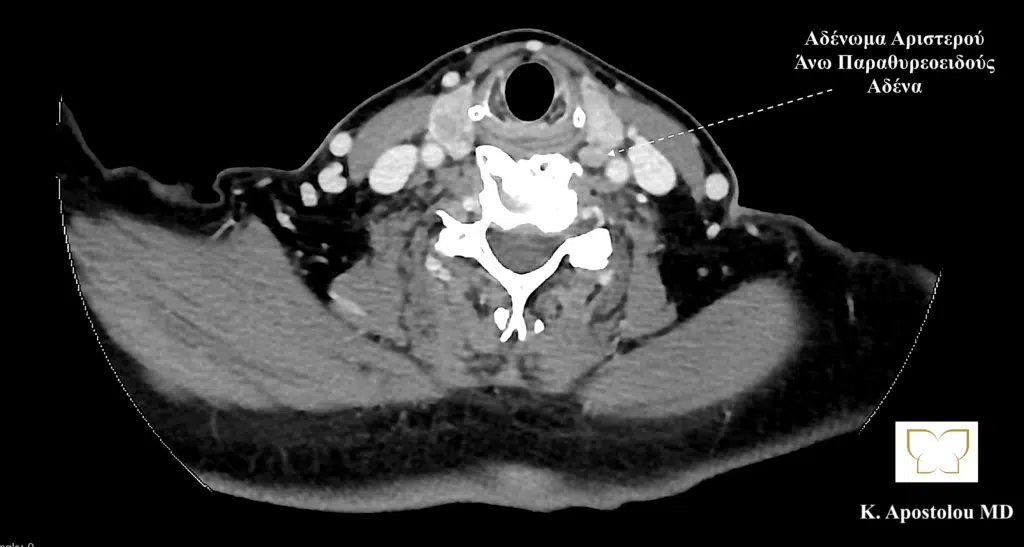

Ομοίως, η αξονική τομογραφία αποκάλυψε την παρουσία τριών αδενωμάτων παραθυρεοειδούς και πιο συγκεκριμένα του δεξιού άνω παραθυρεοειδούς, του αριστερού άνω παραθυρεοειδούς και του δεξιού κάτω παραθυρεοειδούς αδένα, καθώς και την παρουσία διόγκωσης του θυρεοειδούς αδένα με κατάδυση αυτού στο ανώτερο μεσοθωράκιο και την παρουσία πολλαπλών όζων θυρεοειδούς (καταδυόμενη πολυοζώδης βρογχοκήλη).

αδενωμα αριστερου ανω παραθυρεοειδους